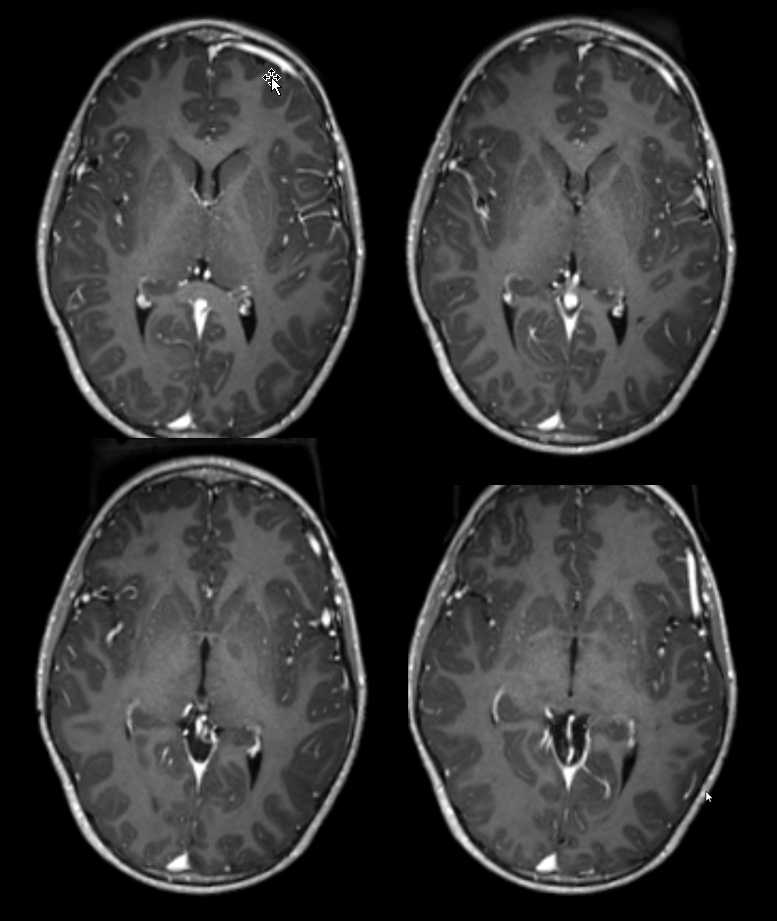

All of the above anatomic knowledge can become very useful in evaluation of venous thrombosis. Numerous collateral pathways develop in this setting attempting to compensate for the loss. The most dramatic cases usually involve the largest channel — the superior sagittal sinus. In this case, a man presented with what initially was thought to be vasculitis-related brain hemorrhage. Subsequent workup led to an angiogram, where sagittal sinus thrombosis with extensive trans-cerebral and trans-osseous emissary vein collateral channels was seen. In retrospect, these findings were present on the patient’s earlier contrast MRI. “Venovibe” or other contrast-enhanced MR venograms can very sensitive, particularly when interpreted with the appropriate index of suspicion. Noncontrast 2-D time of flight MRV I consider to be next to useless as a problem-solving technique. Any thin-slice postcontrast T1 study is vastly superior.